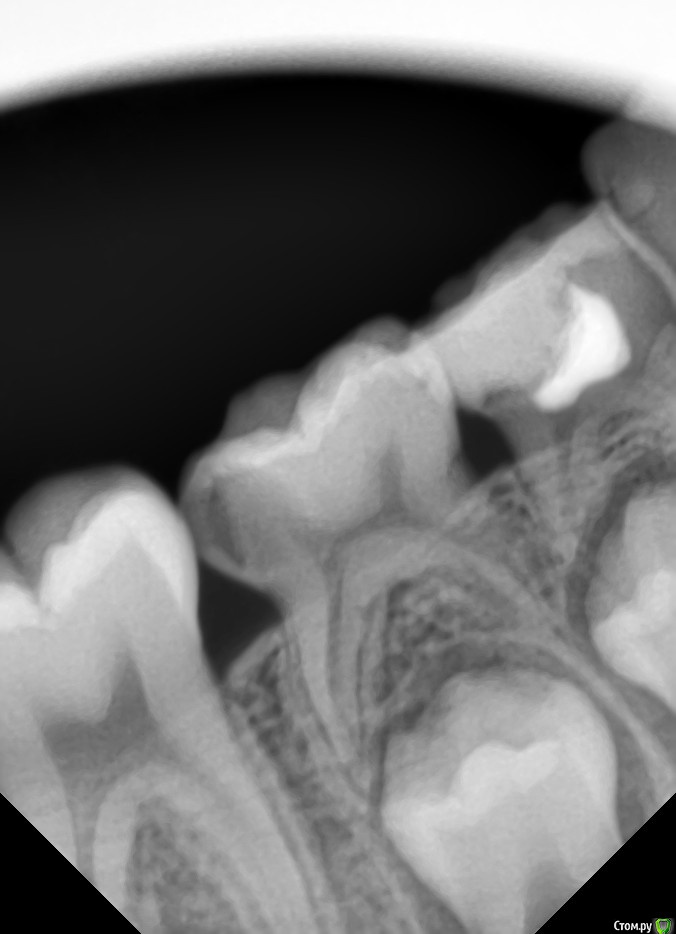

anytka Опубликовано 14 октября, 2015 Поделиться Опубликовано 14 октября, 2015 (изменено) 1.6 направила на удаления т.к вижу на снимке трещину между щечным кормить хирург сказал лечить. Толи он не видит. Толи я вижу что то не то. Просто получить так. Что снимок сделали у нам в поликлинике. А хирург у нас в отпуске. И я отправила в другую стоматологию на удаления к хирургу. Тот вызвал детского стоматолога, и терапевта и они пришли к мнению что надо лечить т.к ребёнок удалять жалко. Девочке 15 лет. А лечить они вернулись ко мне почему-то Изменено 14 октября, 2015 пользователем anytka Ссылка на комментарий

CRAZYDUCK Опубликовано 15 октября, 2015 Поделиться Опубликовано 15 октября, 2015 (изменено) 1.6 направила на удаления т.к вижу на снимке трещину между щечным кормить хирург сказал лечить. Толи он не видит. Толи я вижу что то не то. Просто получить так. Что снимок сделали у нам в поликлинике. А хирург у нас в отпуске. И я отправила в другую стоматологию на удаления к хирургу. Тот вызвал детского стоматолога, и терапевта и они пришли к мнению что надо лечить т.к ребёнок удалять жалко. Девочке 15 лет. А лечить они вернулись ко мне почему-тоНу , если им ЖАЛЬ, то пусть в той клинике детский стоматолог и лечит, скажите, что у Вас нет методик, позволяющих спасти этот зуб. Не знаю всей картины, но родителям почему-то не жаль было своего ребенка , раз уж до такого довели... Изменено 15 октября, 2015 пользователем CRAZYDUCK 5 Ссылка на комментарий

shevchenko.dr Опубликовано 11 ноября, 2015 Поделиться Опубликовано 11 ноября, 2015 при таком разрушении 16 - надо удалять. потом ортодонтически возможно сдвинуть 17 и 18 "на один вперед". и будут полноценные зубы вместо безнадежного шестого. возможно в будущем и без имплантации обойдется! 1 Ссылка на комментарий